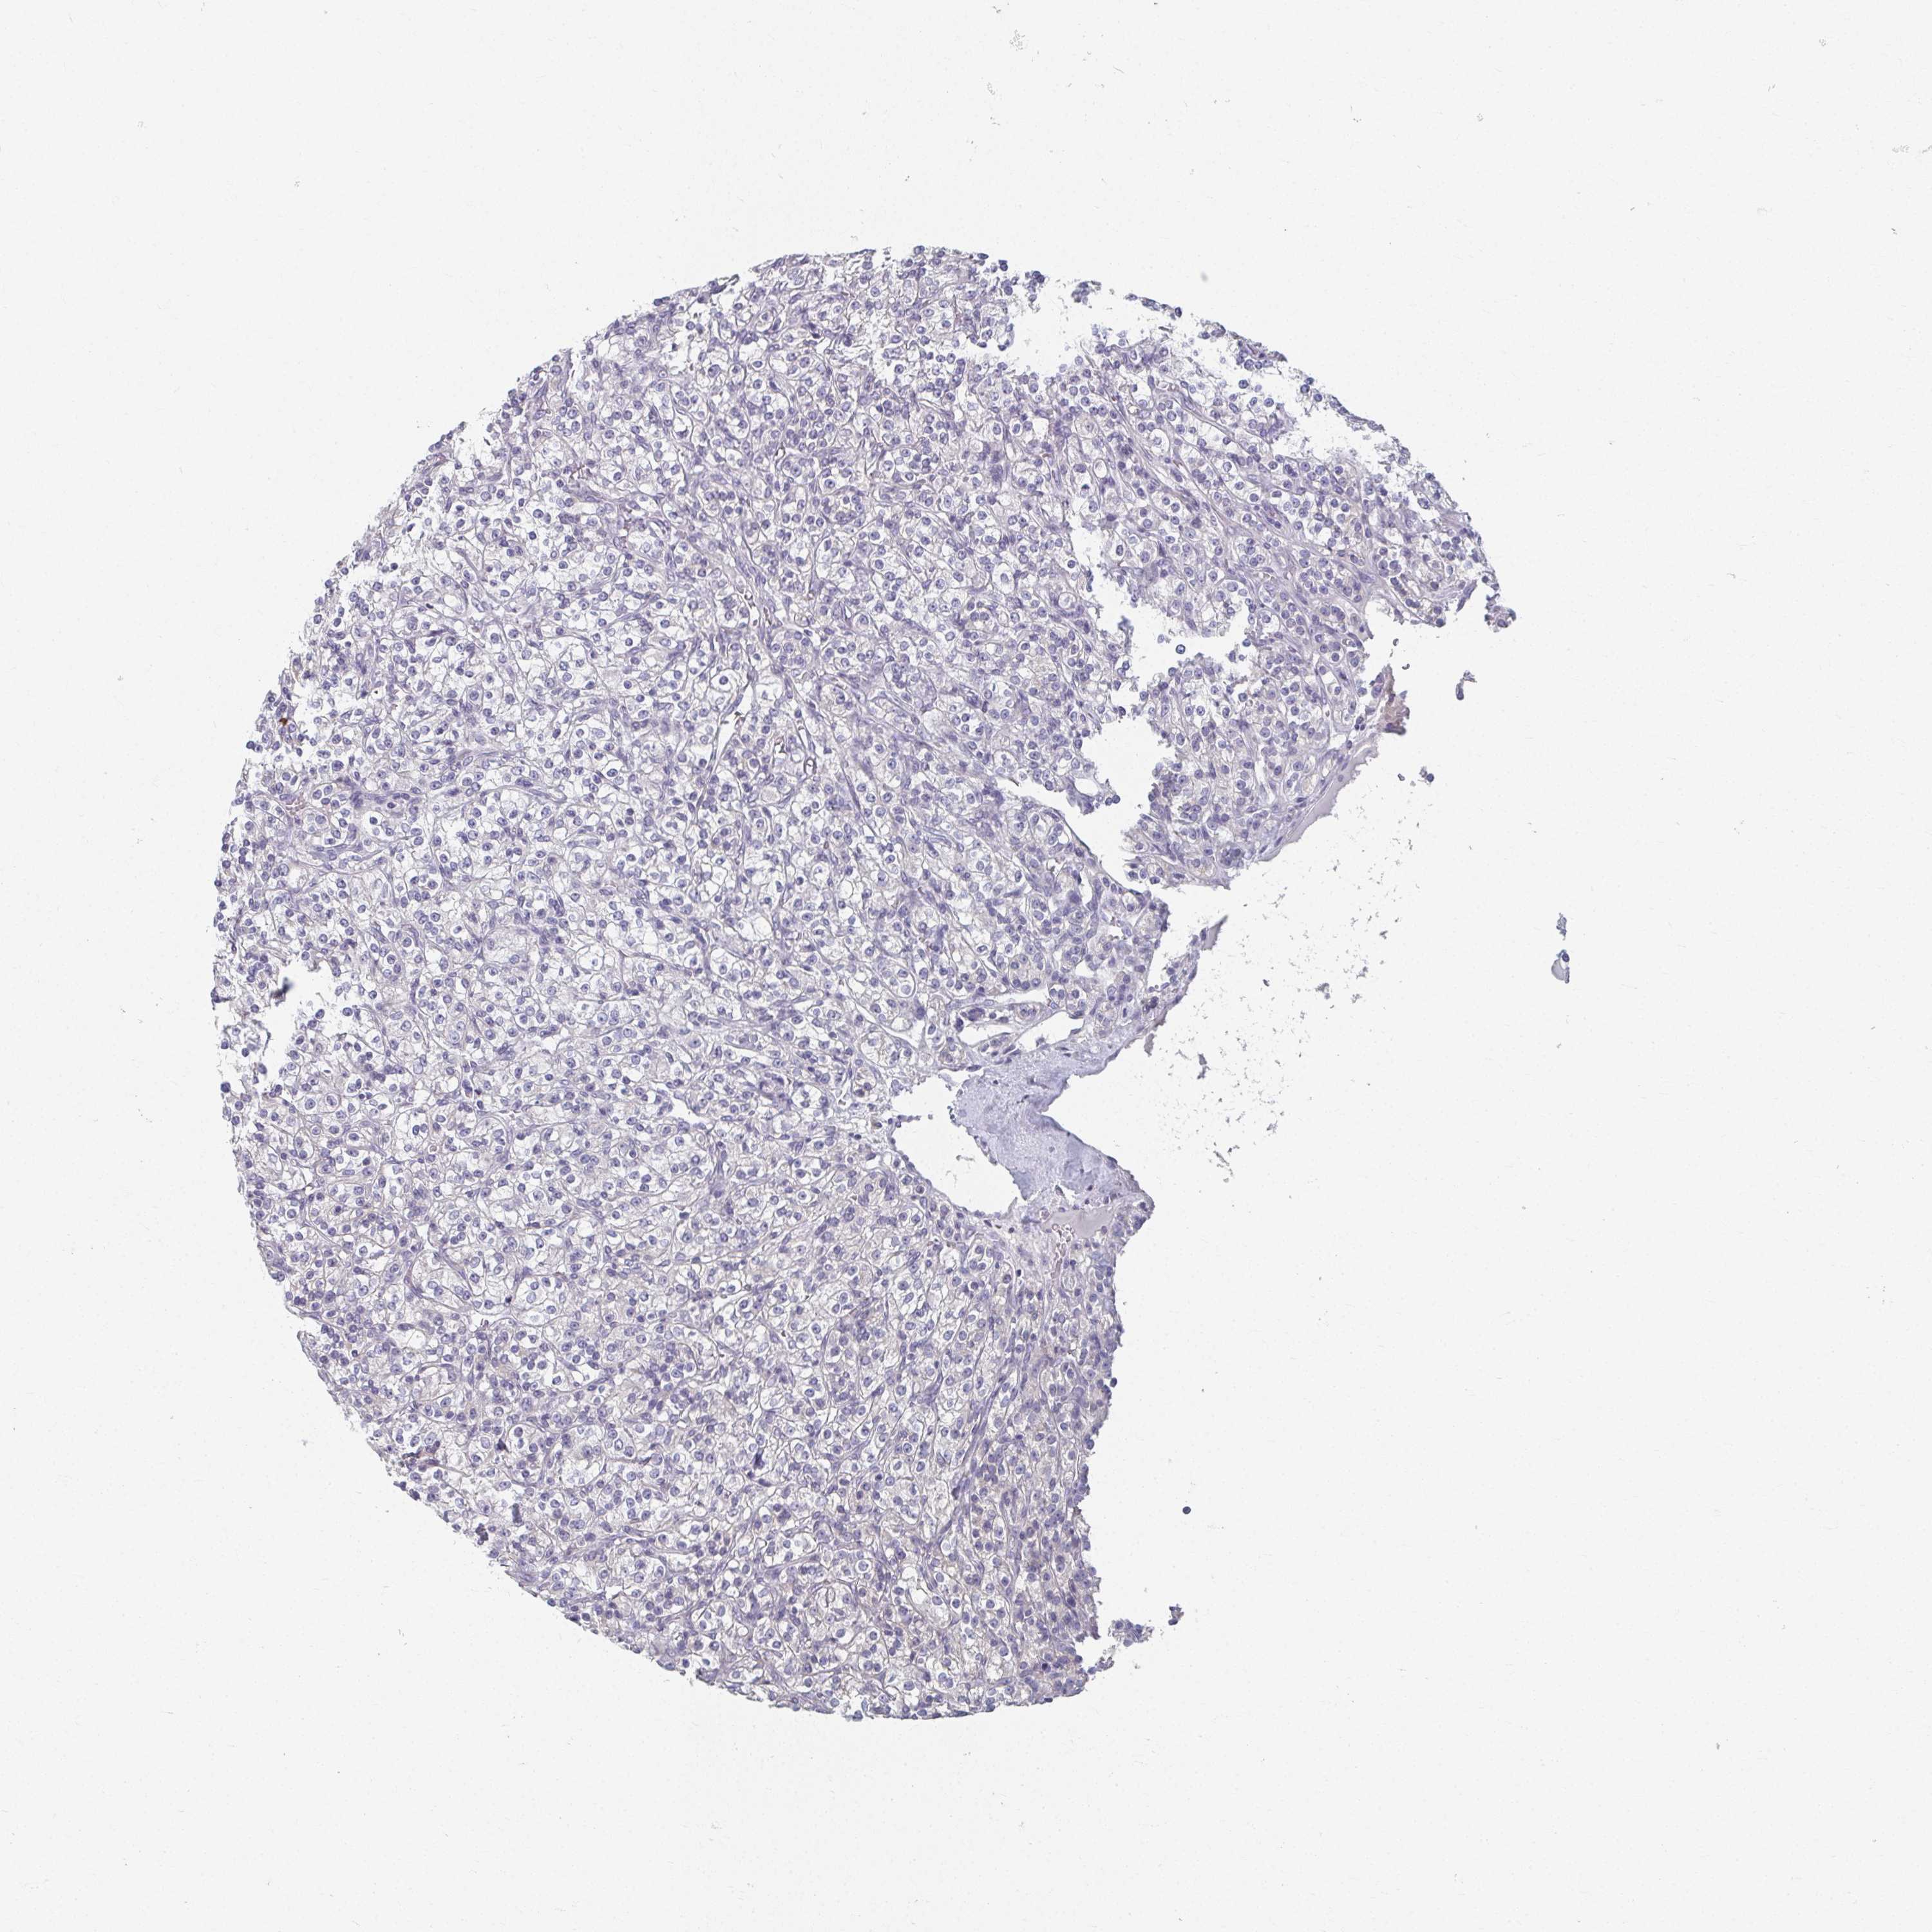

KIDNEY RENAL CLEAR CELL CARCINOMA (VALIDATION) - Interactive survival scatter ploti

The Survival Scatter plot shows the clinical status (i.e. dead or alive) for all individuals in the patient cohort, based on the same data that underlies the corresponding Kaplan-Meier plots. Patients that are alive at last time for follow-up are shown in blue and patients who have died during the study are shown in red.

The x-axis shows the expression levels (FPKM) of the investigated gene in the tumor tissue at the time of diagnosis. The y-axis shows the follow-up time after diagnosis (years). Both axes are complimented with kernel density curves demonstrating the data density over the axes. The top density plot shows the expression levels (FPKM) distribution among dead (red) and alive patients (blue). The right density plot shows the data density of the survived years of dead patients with high and low expression levels respectively, stratified using the cutoff indicated by the vertical dashed line through the Survival Scatter plot. This cutoff is automatically defined based on the FPKM cutoff that minimizes the p-score. The cutoff can be changed by dragging the vertical line or by entering a cutoff value in the square labeled "Current cut-off".

Under the Survival Scatter plot the p-score landscape (black curve; left axis) is shown together with dead median separation (red curve; right axis). Dead median separation is the difference in median mRNA expression between patients who have died with high and low expression, respectively. It is calculated as follows: median FPKM expression of dead patients with high expression - median FPKM expression of dead patients with low expression. This is intended to aid the user in visually exploring custom cutoffs and the associated p-scores and dead median separation.

Individual patient data is displayed and can be filtered by clicking on one or more of the category buttons on the top of the page. Categories describing expression level and patient information include: high, low, alive, dead, female, male and tumor stages. The scale of the x-axis can be toggled between linear and log-scale by clicking on the "x log" button. Mouse-over function shows TCGA ID, patient information and mRNA expression (FPKM) for each patient.

TCGA RNA samplesi

RNA-seq data is reported as average FPKM (number Fragments Per Kilobase of exon per Million reads), generated by the The Cancer Genome Atlas (TCGA) .

Normal distribution across the dataset is visualized with box plots, shown as median and 25th and 75th percentiles. Points are displayed as outliers if they are above or below 1.5 times the interquartile range. FPKM values of the individual samples are presented next to the box plot.

Average pTPM 0.0

Number of samples 100